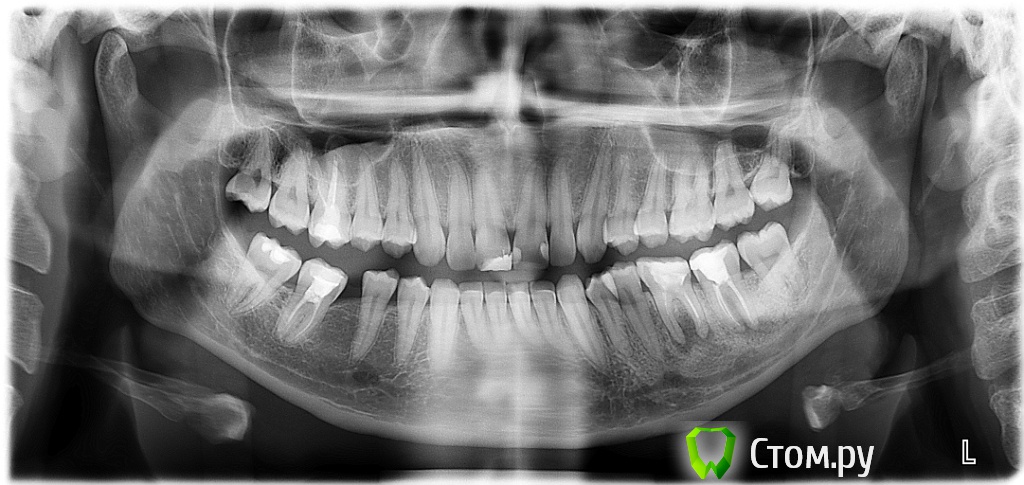

lizza Опубликовано 25 июня, 2014 Поделиться Опубликовано 25 июня, 2014 Добрый вечер! Я девушка мне 26 лет. Сегодня была в стоматологии. Диагноз неутешителен: 2 свища из-за них надо удалить 36-37 зубы и вставлять импланты. Свищи появились постепенно...около 6 месяцев...думала, что они пройдут, а оно вот как оказалось. Уважаемые доктора, прикладываю свой снимок и хочу спросить Ваше авторитетное мнение, неужели ничего нельзя сделать, кроме как удалять? Ссылка на комментарий

dr-krasnov Опубликовано 25 июня, 2014 Поделиться Опубликовано 25 июня, 2014 (изменено) Сделал покрупнее, в 1 квадранте есть сомнительный участок, выделил красным, по 36 и 37, много раз видел как в подобных ситтуациях зубы перелечивались. Это сложно, требует высокой квалификации эндодонтиста и наличия микроскопа. При любом варианте лечения, Вам показано КЛКТ челюстно-лицевой области. А ну и есть лишние 8 ки. http://s019.radikal.ru/i637/1406/7e/0388738e7075.jpg Изменено 25 июня, 2014 пользователем dr-krasnov Ссылка на комментарий

Bier Опубликовано 25 июня, 2014 Поделиться Опубликовано 25 июня, 2014 наверху проблемы у 16з 100% есть. Зубы можно перелечить с большой вероятностью успеха. В умелых руках конечно. Ссылка на комментарий

art700 Опубликовано 25 июня, 2014 Поделиться Опубликовано 25 июня, 2014 По-мойму проблема в 16, кт, либо прицельный для начала бы сделать Ссылка на комментарий

Korel Опубликовано 26 июня, 2014 Поделиться Опубликовано 26 июня, 2014 При удалении какой должен быть микроскоп? Никакой. Другой вопрос, мож. ещё рано удалять. КЛКТ мне не назначили, возможно ли лечение без него? Да. но значит. удобнее и информативнее с ним т.к. можно "повертеть" Ваши зубки со всех сторон и рассмотреть каждый мм. А что сомнительного в участоке в 1 квадранте? http://s006.radikal.ru/i214/1406/3b/b9dc1a606cb6.jpg 16 нужд. в перелечке, которой можно заняться после решения проблем с 36-37 Почему 8 ки лишние? Пока с этим можно не заморачиваться , и решать этот вопрос после решения вопросов с 36-37 и 16 Можно ли подождать с лечением 3 недели? Свищи появились постепенно...около 6 месяцев...думала, что они пройдут, Ничего не напоминает? По этому вопросу надо смотреть ОЧНО. Ссылка на комментарий

DokDent Опубликовано 26 июня, 2014 Поделиться Опубликовано 26 июня, 2014 а 4.7 тоже хочет перелечиться 1 Ссылка на комментарий